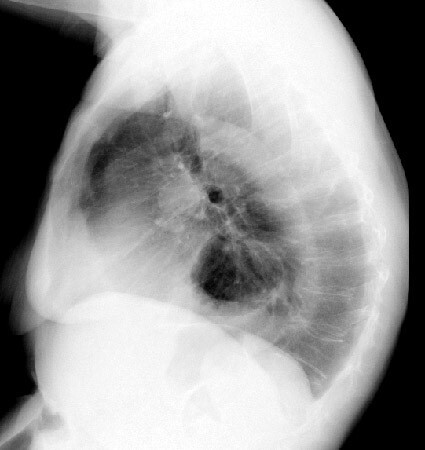

Wilms tumor/nephroblastoma

-asymptomatic abdominal mass

-2-5yo

-hematuria

-HTN

-Mets to bone and lung

-if pulm mets pt will require whole lung radiation

-does NOT cross midline

-DX:

-US

-CT scan will differentiate it from a neuroblastoma

-Tx-

-nephrectomy with exploration of the other kidney and peritoneum.

-Tumor MUST NOT rupture when being taken out -> worsens prognosis.

-Chemo in all pts -> Actinomycin and Vincristine -> unless Stage 1 or < 500 g in wt